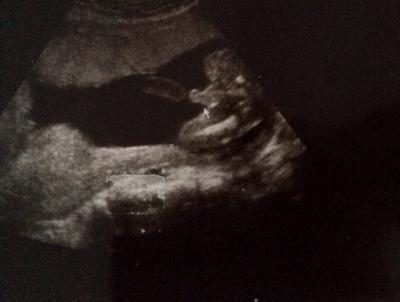

Hallo, Das Geschlecht ist doch Eindeutig oder?

Also das hat grad sogar mein 4 jähriger Sohne erkannt. Eindeutiger geht's nicht.

Sehr zeigefreudig der junge Mann LG Mila

Da zeigt aber jemand was er hat mein Sohn war damals auch so ;-) Glückwunsch zum Jungen!

Ich war felsenfest überzeugt das es ein Mädchen wird :) Naja wichtig ist das er gesund ist und bleibt.

Eindeutiger gehts nicht! Macht er sogar Pipi gerade? Schönen Abend noch! Lg Daniela